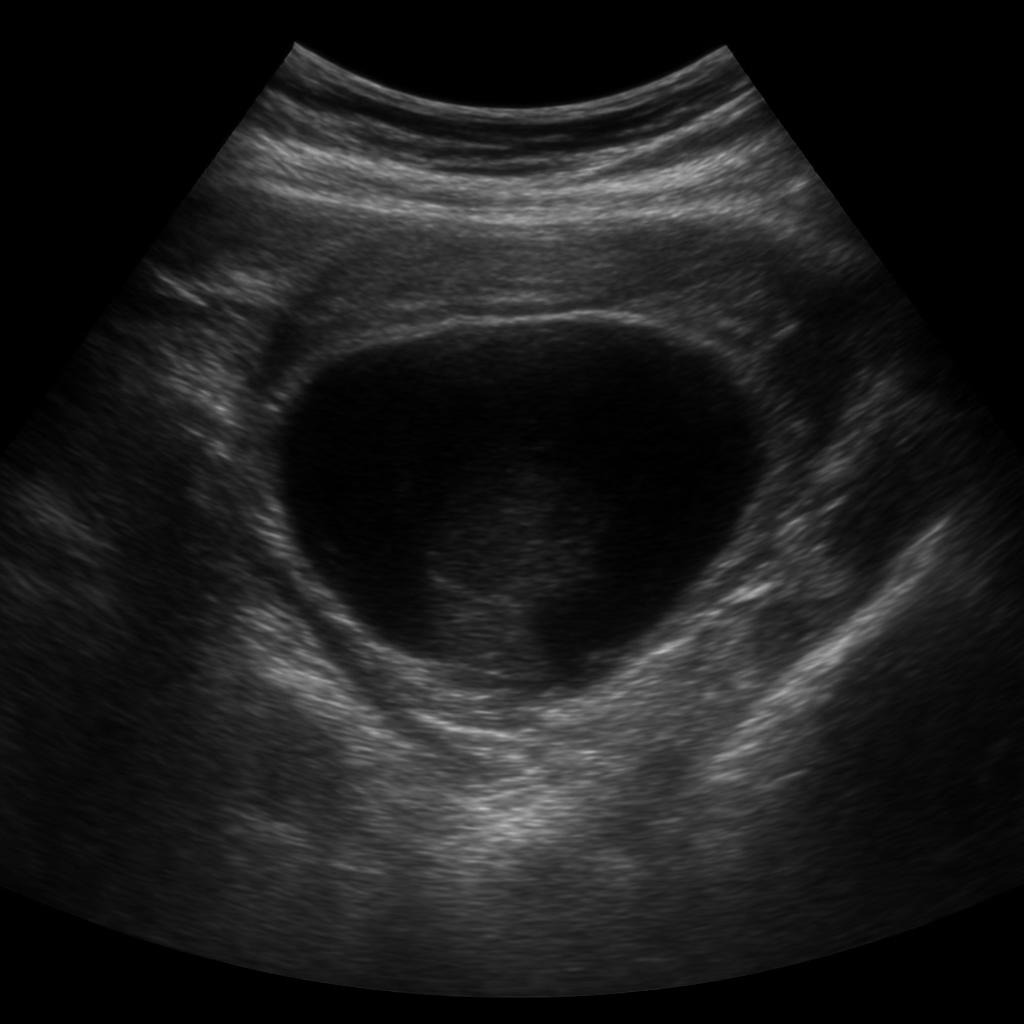

Ultrahang vizsgálatok a XIII. kerületben – gyors, fájdalommentes diagnosztika

A Vitályos Rendelőben korszerű ultrahangos képalkotó vizsgálatokat végzünk a XIII. kerületben, a Róbert Károly körút 40. szám alatt.

Az ultrahang sugárterhelés nélküli, biztonságos, fájdalommentes módszer, amely gyors és megbízható információt ad a belső szervek, lágyrészek és ízületek állapotáról.

Hasi és kismedencei ultrahang